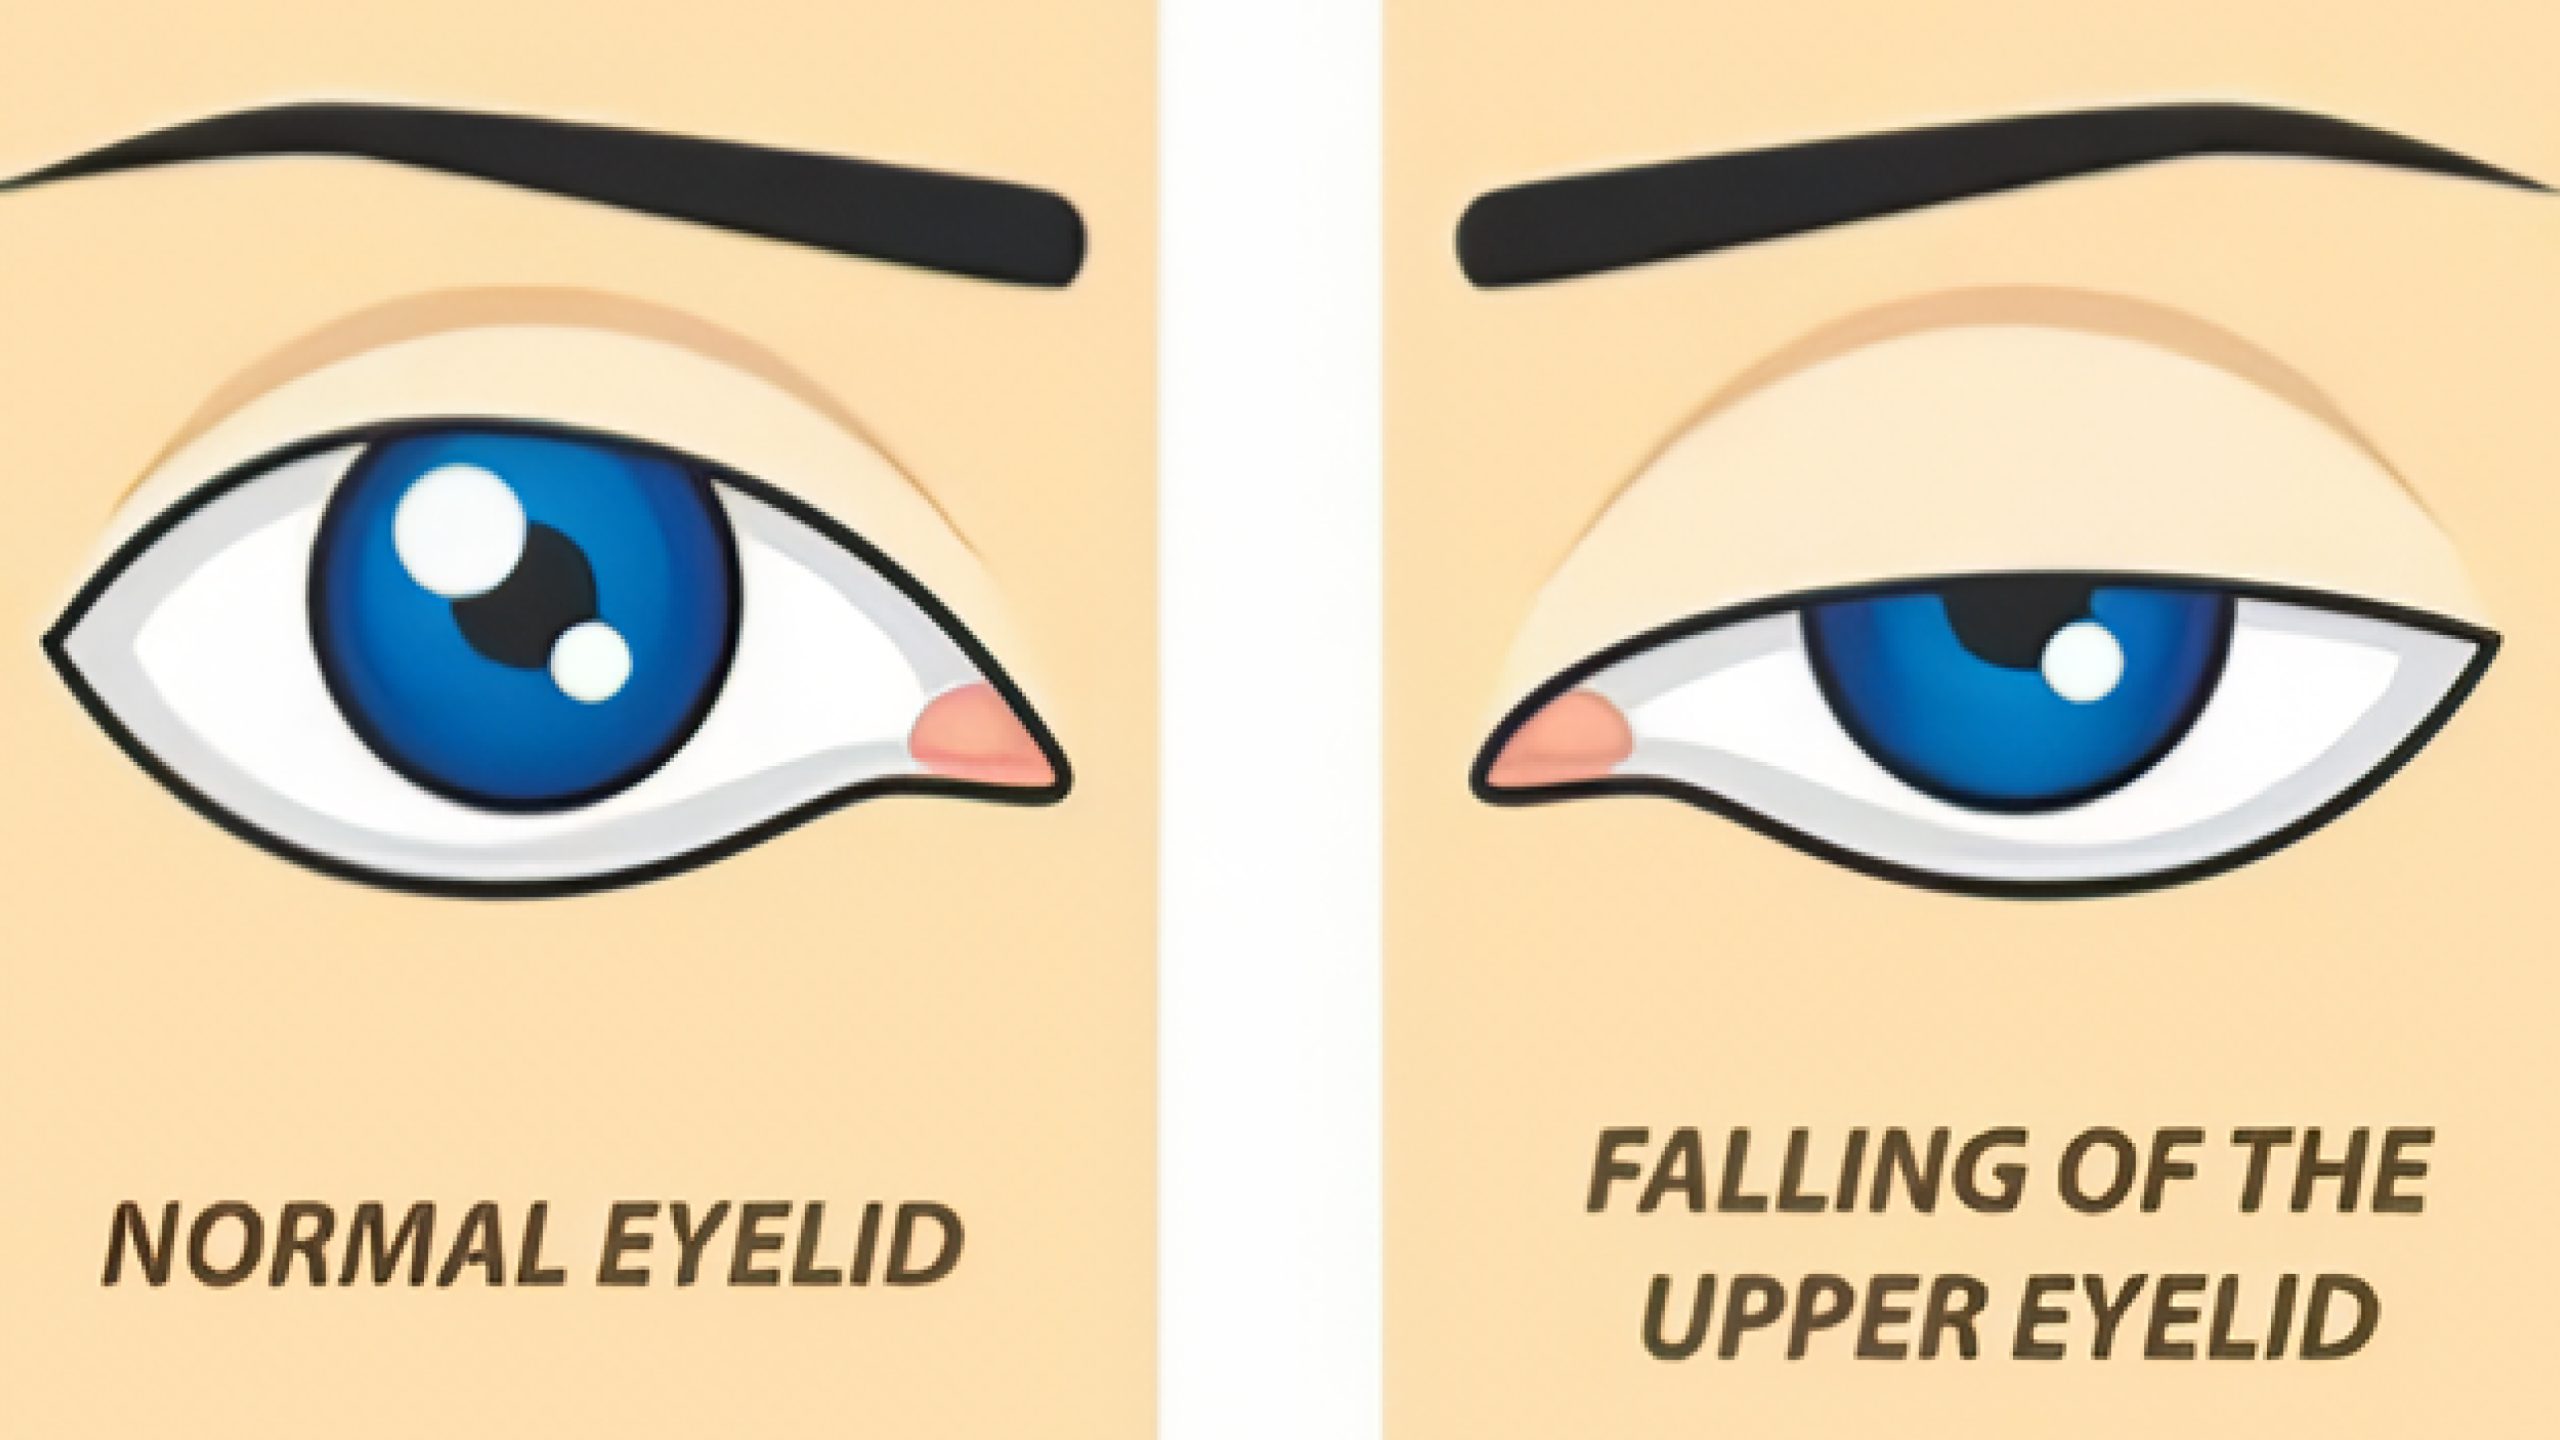

上睑下垂

此病中医称为“上胞下垂”,指上脸提肌功能障碍,以致上臉睁开无力,遮住瞳孔或眼检闭合、仅留一隙而影响视物的眼病。本病有先天性和后天性之分,可双眼或单眼发病。先天性多属动眼神经上睑提肌分支或动眼神经核发育不全所致(多为双眼);后天性可因外伤、炎症、肿块等局部因素,临床亦可见动眼神经麻痹、重症肌无力、精神因素等所致。西医治疗手法通常为手术,取决于病因和严重程度。若发现明显下垂,尤其是突然发生或伴有其他症状,请寻求专业眼科护理。

中医将上胞下垂的病因病机归纳为:先天禀赋不足,命门火衰,脾阳不足,导致睑肌发育不全,胞睑乏力不能升举;或脾虚中气不足,清阳不升,睑肌失养,上胞无力提举;或脾虚聚湿生痰,风邪客睑,风痰阻络,胞睑筋脉迟缓不用而下垂。对于先天性的上睑下垂,如果药效不理想,建议进行手术矫正;对于后天性的上睑下垂,可以在中药内服的基础上配合针灸调理。